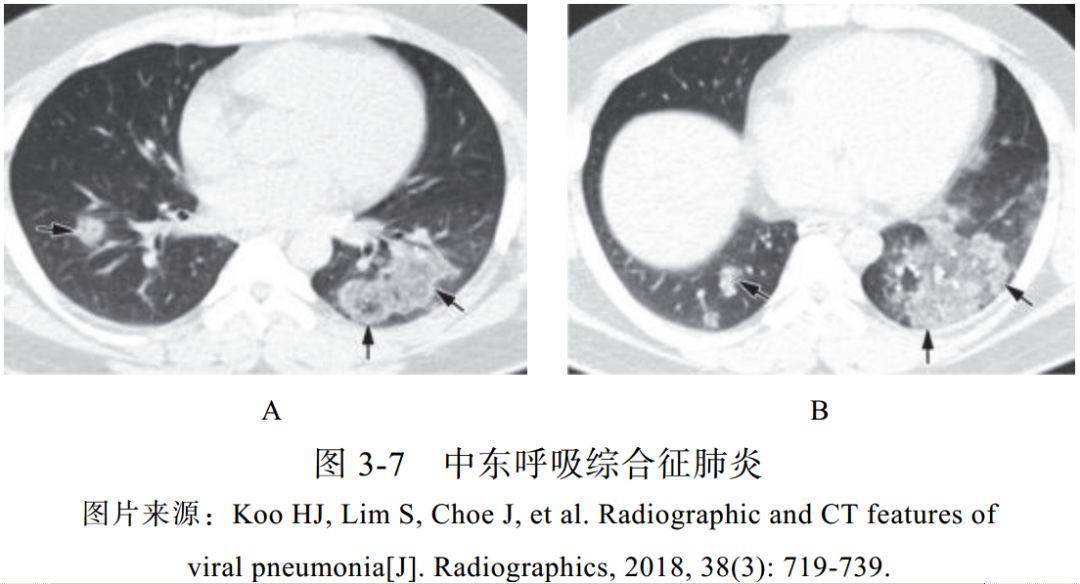

(七)中东呼吸综合征

中东呼吸综合征冠状病毒(MERS-CoV)是 β 冠状病毒的新成员,初次发现是在 2012 年,宿主主要来源于骆驼,临床症状与其他下呼吸道感染类似,发展迅猛,进展为急性呼吸窘迫综合征、多脏器功能衰竭等,死亡率高

影像学表现:

(1)包括胸膜下和基底部气腔病变(图 3-7A),伴广泛的 GGO和实变(图 3-7B)

(2)空洞罕见

(3)死亡患者常见胸腔积液和气胸

(4)痊愈后,可遗留纤维化改变